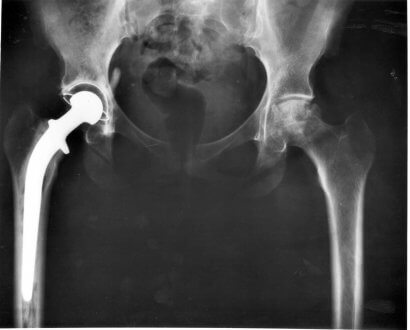

Quando um cão começa a sentir fraqueza ou tem paralisia dos membros traseiros, as razões podem ser variadas. As possibilidades são neurológicas, ortopédicas ou sintomáticas. Quando as causas são neurológicas, ocorre o que se conhece como paraparesia ou paraplegia aguda.

A causa mais frequente desse tipo de paralisia que começa com a fraqueza das patas traseiras é a doença degenerativa do disco invertebral. Estranhamente, ela é muito comum em cães e quase inexistente em gatos.

Essa doença é conhecida como uma hérnia de disco Hansen I. Há também o tipo Hansen II, mas essas têm um processo mais crônico, por isso não são tão agressivas.

As hérnias Hansen I afetam principalmente as raças Dachshund, Cocker spaniel, Beagle, Pequinês e Shih Tzu, entre outras. Se você acha que seu cão sofre de alguma hérnia ou se ele foi diagnosticado com a doença, não demore a visitar um neurologista veterinário.

Quanto mais tempo se passa sem tratamento, pior podem ser as consequências. Enquanto que se o problema for descoberto a tempo, pode ser solucionado por meio de uma cirurgia.

Cirurgia para a hérnia Hansen I, sim ou não?

Não somos nós que devemos responder a essa pergunta, mas podemos dar informações necessárias para que você tome uma decisão. Primeiramente, devemos saber que nem todas as cirurgias são bem-sucedidas, embora uma grande porcentagem obtenha êxito se o problema for diagnosticado a tempo.

Tudo depende do que o neurologista disser, pois a cirurgia pode ser evitada se o animal puder andar mesmo com a hérnia. Nessa situação, o profissional terá diagnosticado uma protrusão de disco.

O tratamento durará algumas semanas e exigirá repouso estrito. Para ajudar na resolução, suplementos de corticoides e protetores gástricos podem ser receitados.

Vale destacar que, se você decidir fazer a cirurgia, deve saber que o animal precisará de várias semanas em repouso total ou as possibilidades de retroceder ao quadro anterior podem ser grandes.